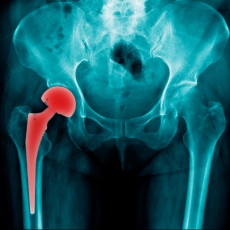

El reemplazo de cadera es una cirugía para personas con daños severos en la cadera. Si otros tratamientos como la fisioterapia, analgésicos o ejercicio no ayudan, la cirugía puede ser una opción. ¿En qué consiste el procedimiento? Entérate aquí ow.ly/gCZe50B9Ipc

Reemplazo de cadera: MedlinePlus en español